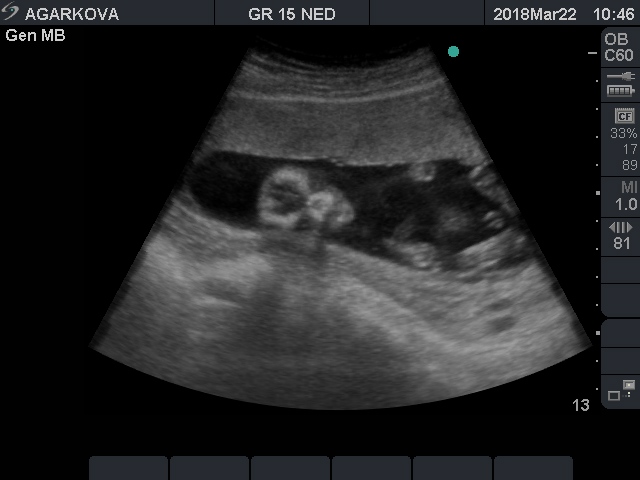

Мальчик или не мальчик?...

Мальчик

Мальчик :) Я на нашем видео прям вижу кофейное зернышко :) А тут вон достоинство!

Нет, ну на последнем фото определенно мальчик!!И мошонка и писюн хорошо видны.У меня похожие фотки причандалов от двух сыновей))